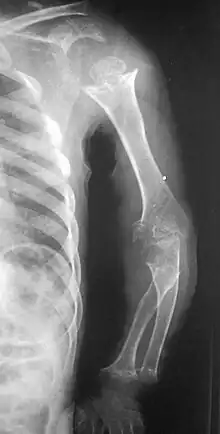

| Pseudoachondroplasia. Shoulders and Humeri. Note the dysplastic proximal humeral epiphyses, metaphyseal broadening, irregularity and metaphyseal line of ossification. These changes are collectively known as "rachitic-like changes". Lesions are bilateral and symmetrical. | |

- Together with rhizomelic limb shortening, the presence of epiphyseal-metaphyseal changes of the long bones is a distinctive radiologic feature of pseudoachondroplasia.

- Dysplastic/hypoplastic epiphyses especially of shoulders and around the knees.

- Metaphyseal broadening, irregularity and metaphyseal line of ossification. These abnormalities that are typically encountered in proximal humerus and around the knees are collectively known as "rachitic-like changes".

- Radiographic lesions of the appendicular skeleton are typically bilateral and symmetric.